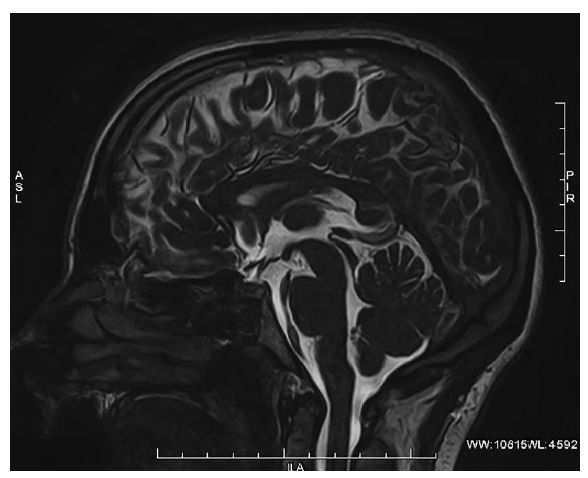

По структуре кисты могут быть однокамерными и многокамерными. По размеру в литературе принято выделять кисты менее 10 мм и более 10 мм. Мы выделяем ещё один вариант, который не описан в литературе, когда в достаточно гомогенной паренхиме эпифиза визуализируются множественные мелкие, отдельно лежащие кисты диаметром до 2 мм, и называем это мелкокистозной дегенерацией (рис.2).

Рис. 2. МРТ головного мозга, FIESTA-ИП. Срединный сагиттальный срез. Эпифиз нормальной величины, мелкие кисты в его структуре. / Fig. 2. Brain MRI, FIESTA sequence. Midline sagittal section. Pineal gland is of normal size, with small cysts in its structure.

Причина возникновения мелкокистозной дегенерации эпифиза остаётся до конца не ясной. Одной из вероятных причин, по нашему мнению, является расширение периваскулярных пространств в ткани эпифиза, что требует дальнейшего изучения.